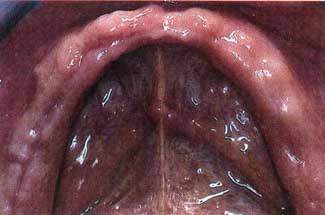

Une semaine après l'intervention chirurgicale, le contrôle habituel doit être effectué. Il faut noter la reprise complète, avec ni ulcères de la bouche, ni les processus inflammatoires résultant (fig. 20 et 21 ). Ce tableau clinique est confirmé par les suivis effectués 2 et 4 semaines plus tard, et il est tout à fait clair comment le matériel peut encore accomplir sa tâche (fig. 22 , 23 , 24 , 25 , 26 et 27 ).